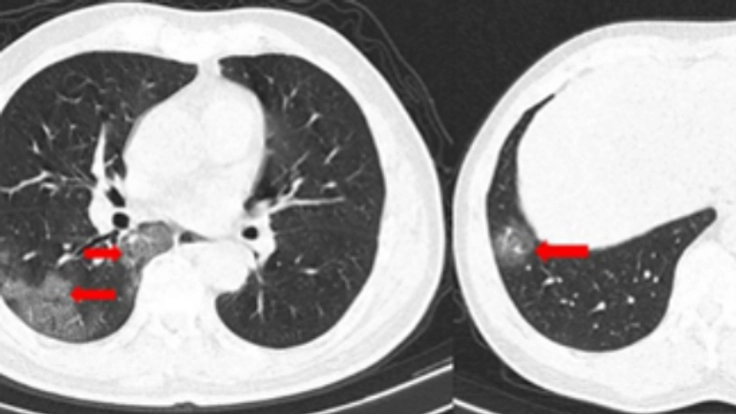

重症化を防ぐためには、早期に肺炎を発見する必要がありますが、胸部レントゲンでは早期の肺炎を発見するのは困難です。(お示しの胸部CT像のように肝臓や心臓の裏に隠れた微細な肺炎の場合、胸部レントゲンのみでの診断は困難を極めます)

その為、肺炎を早期に発見するにはCTが有効です。